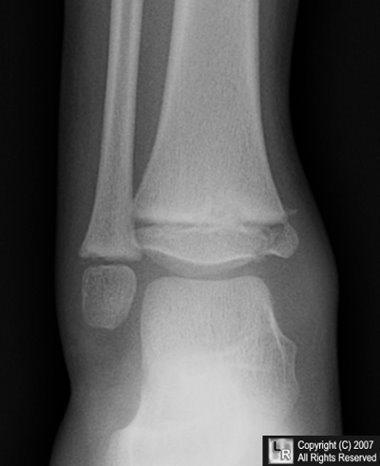

Case of the Week 530

What is the most likely diagnosis?

• 10 year-old with pain in ankle after fall

Frontal radiograph of the ankle

1. Salter-Harris I fracture

2. Salter-Harris II fracture

3. Salter-Harris III fracture

4. Salter-Harris IV fracture

5. Salter-Harris V fracture

Salter-Harris IV fracture

General Considerations

• The epiphyseal plate (physis or growth plate) is the weakest part of the bone to shearing injuries

• The Salter-Harris classification is a means of categorizing epiphyseal plate fractures and provides clues to their prognosis

• All such these fractures, by definition, involve or extend through the epiphyseal plate so that all such fractures occur in children before the epiphyseal plate closes